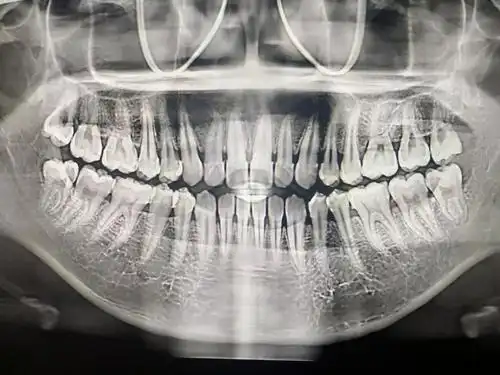

其实去年我就牙疼过,后来去拍牙片就发现有两颗智齿了,从我的牙片来看